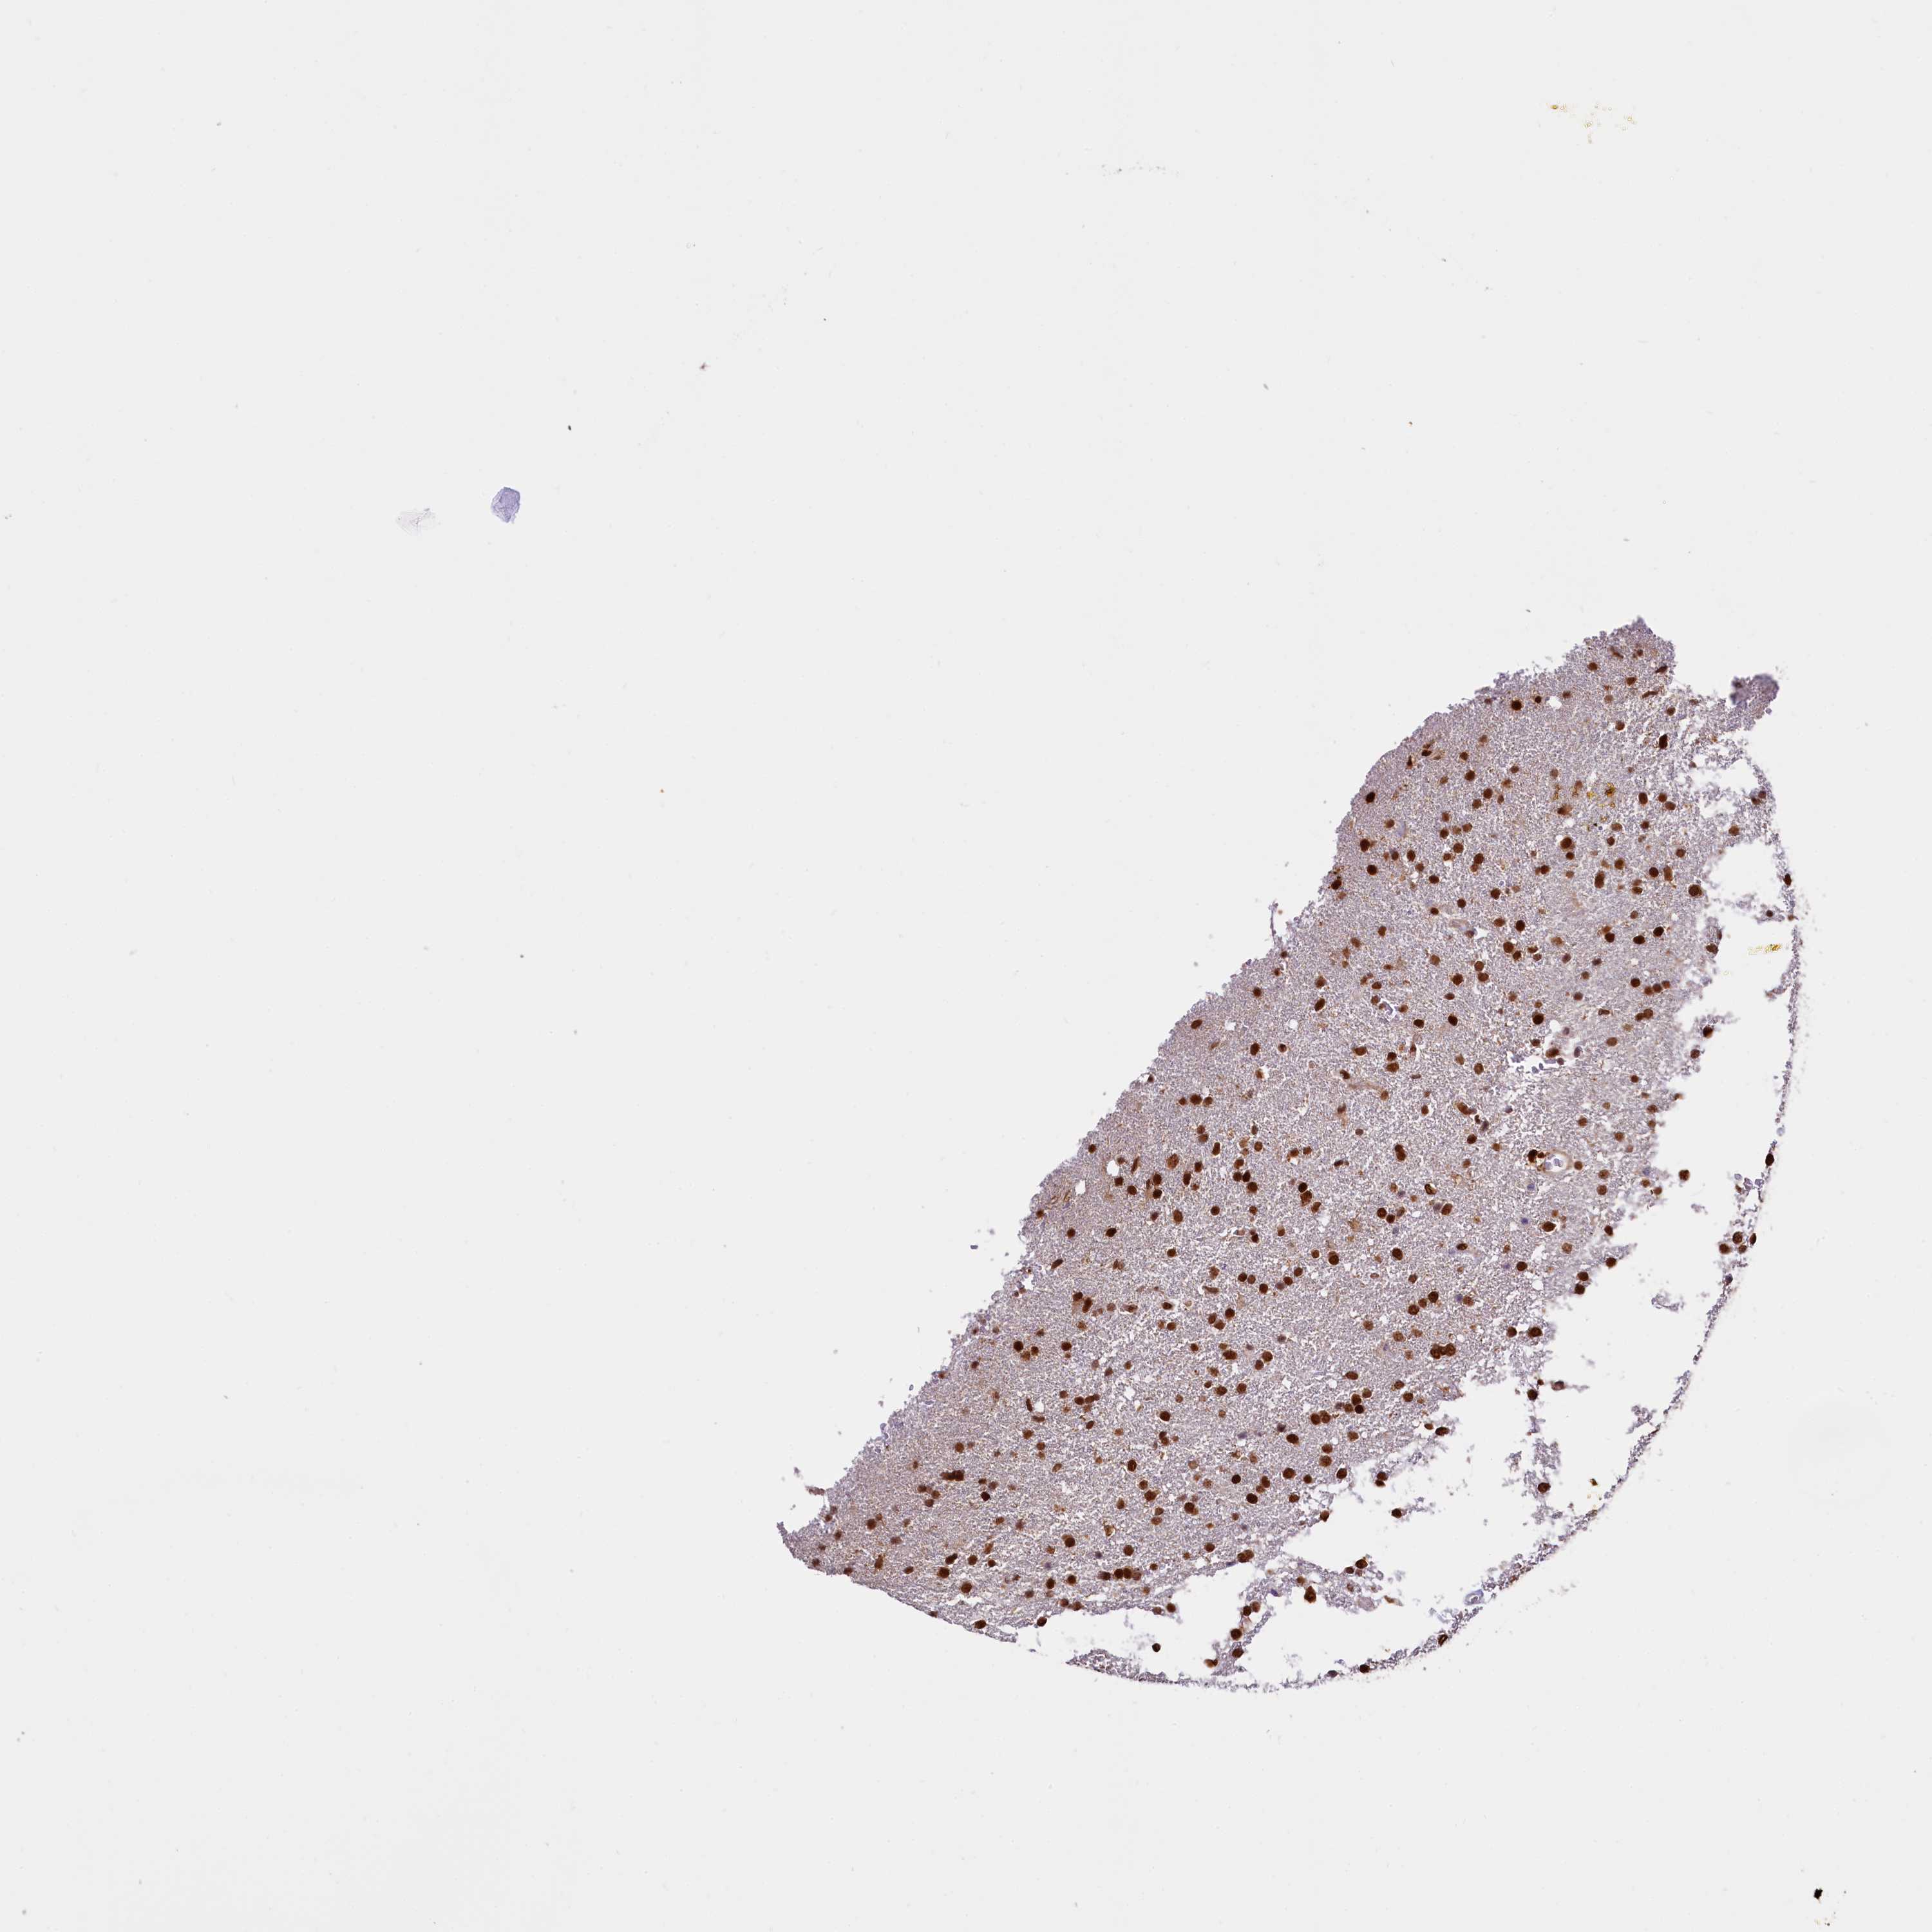

GLIOMA - Protein expressioni

A mouse-over function shows sample information and annotation data. Click on an image to view it in a full screen mode. Samples can be filtered based on level of antibody staining by selecting one or several of the following categories: high, medium, low and not detected. The assay and annotation is described here.

Note that samples used for immunohistochemistry by the Human Protein Atlas do not correspond to samples in the TCGA dataset.

Antibody stainingi

Antibody staining in the annotated cell types in the current human tissue is reported as not detected, low, medium, or high, based on conventional immunohistochemistry profiling in selected tissues. This score is based on the combination of the staining intensity and fraction of stained cells.

Each image is clickable and will lead to virtual microscopy that enables deeper exploration of all samples and also displays staining intensity scores, fraction scores and subcellular localization as well as patient and tissue information for each sample.

Antibody HPA039513

Antibody HPA040015

Staining

High

Medium

Low

Not detected

Intensity

Strong

Moderate

Weak

Negative

Quantity

>75%

75%-25%

<25%

None

Location

Nuclear

Cytoplasmic/membranous

Cytoplasmic/membranous,nuclear

Glioma, malignant, High grade

Glioma, malignant, Low grade